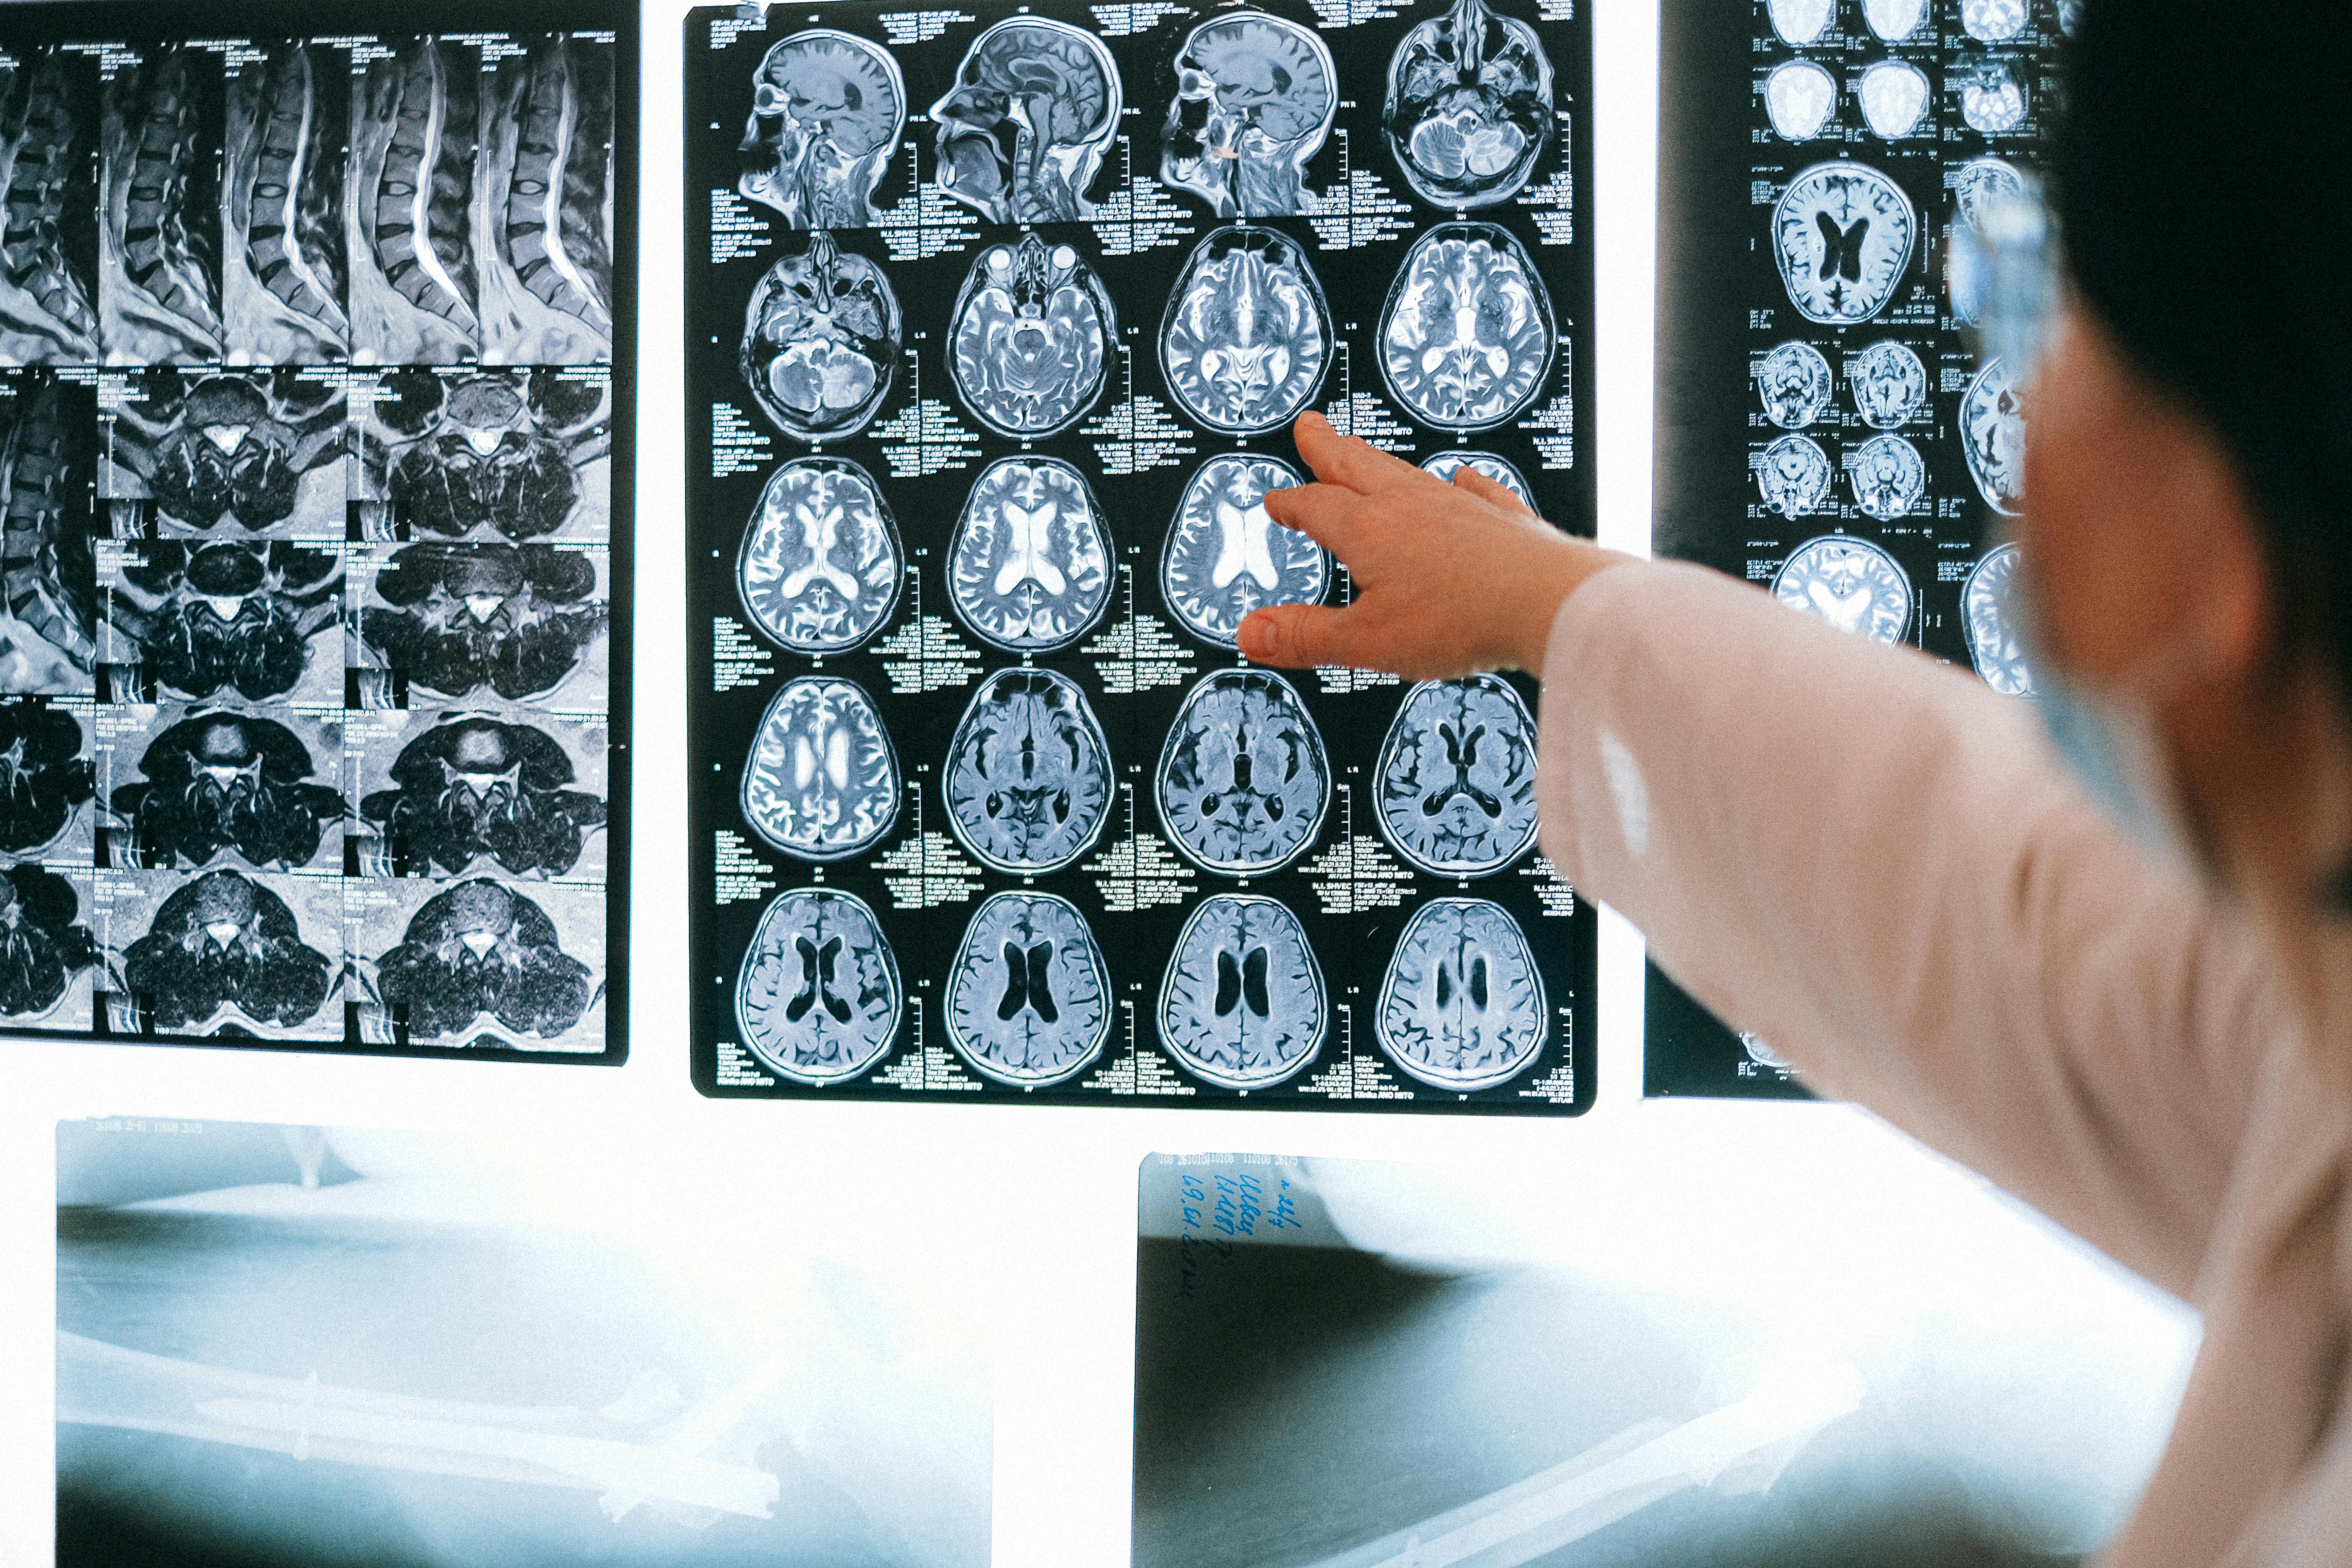

셋째, 정기적으로 뇌혈관 건강을 체크하고, 특히 가족력이 있는 경우 뇌동맥류 등 잠재 리스크에 대한 영상검사(필요시) 고려해야 합니다.